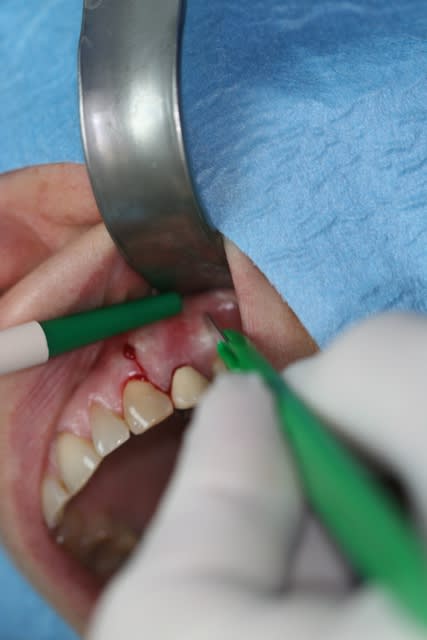

Patiente présente une perte alvéolaire de la table externe suite à fracture radiculaire.

J'ai réalisé un lambeau tracté coronairement mais je pense que certains auraient peut-être réalisé un lambeau conjonctif palatin.

Quels auraient été vos tracés d'incisions ?

Incision1 r6yqb4 - Eugenol

Incision2 dd0trg - Eugenol